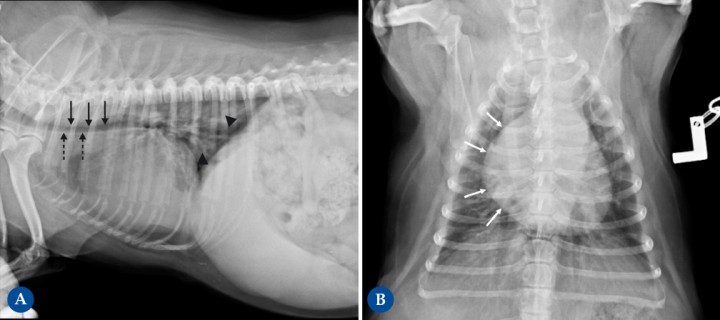

<p> West Highland White Terrier macho castrado de 14 años presentado por tos crónica. En la proyección lateral derecha (Fig. 3A), la silueta cardíaca está aumentada de tamaño, ocupando 4 espacios intercostales (ref<2,5-3), produciendo un desplazamiento dorsal de la tráquea, adquiriendo una posición paralela respecto a la columna vertebral (flechas negras punteadas). El aumento del apoyo esternal en la vista lateral y apariencia de D invertida en la proyección DV de la Fig. 3B (mayor engrosamiento con una forma más redondeada, flechas blancas) son consistentes con cardiomegalia derecha. El cuadrante craneodorsal amplio está causado por dilatación del atrio derecho. Considerando la raza y los cambios en el parénquima pulmonar asociados, con un aumento de la opacidad pulmonar con áreas de patrón alveolointersticial, más marcado en lóbulos caudodorsales (cabezas de flecha) compatibles con posible fibrosis pulmonar, los cambios cardíacos son compatibles con un <em>cor pulmonale</em> por hipertensión pulmonar secundaria a la enfermedad respiratoria, afectando predominantemente al corazón derecho. También se detecta redundancia de la membrana dorsal de la tráquea (flechas negras), sugestivo pero no diagnóstico de colapso de tráquea.</p>

West Highland White Terrier macho castrado de 14 años presentado por tos crónica. En la proyección lateral derecha (Fig. 3A), la silueta cardíaca está aumentada de tamaño, ocupando 4 espacios intercostales (ref<2,5-3), produciendo un desplazamiento dorsal de la tráquea, adquiriendo una posición paralela respecto a la columna vertebral (flechas negras punteadas). El aumento del apoyo esternal en la vista lateral y apariencia de D invertida en la proyección DV de la Fig. 3B (mayor engrosamiento con una forma más redondeada, flechas blancas) son consistentes con cardiomegalia derecha. El cuadrante craneodorsal amplio está causado por dilatación del atrio derecho. Considerando la raza y los cambios en el parénquima pulmonar asociados, con un aumento de la opacidad pulmonar con áreas de patrón alveolointersticial, más marcado en lóbulos caudodorsales (cabezas de flecha) compatibles con posible fibrosis pulmonar, los cambios cardíacos son compatibles con un cor pulmonale por hipertensión pulmonar secundaria a la enfermedad respiratoria, afectando predominantemente al corazón derecho. También se detecta redundancia de la membrana dorsal de la tráquea (flechas negras), sugestivo pero no diagnóstico de colapso de tráquea.